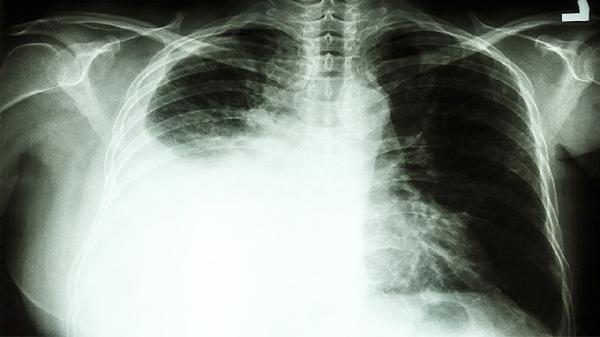

肺部肿瘤占位影响气体交换时,动脉血氧分压下降可致脑缺氧性头晕。患者多伴有呼吸困难、口唇发绀。可通过吸氧改善症状,同时使用注射用培美曲塞二钠、卡铂注射液等化疗药物控制肿瘤进展。